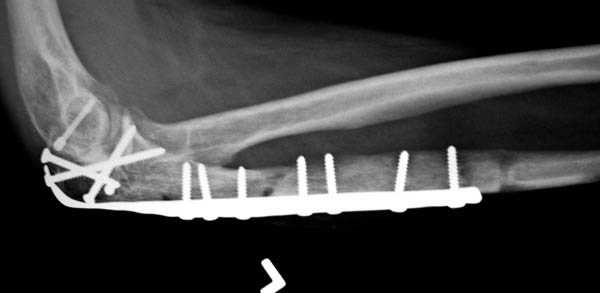

Здесь выставлены несколько случаев и варианты фиксации локтевого отростка, некоторые в комбинации с другими переломами.

2 вариант

перелом локтевого отростка с переломом головки лучевой кости (использованы 2 мм шурупы)